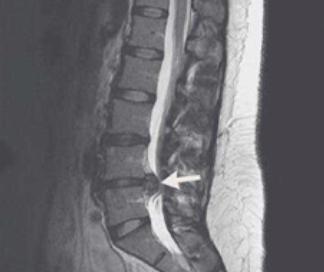

まず、腰痛というと、ほとんどの人は腰椎椎間板ヘルニアという一つの病気を思い浮かべますが、実は腰椎椎間板ヘルニアまでいかなくても、腰椎椎間板が膨隆している場合も腰痛になることがあります。この場合、その人は特に腰痛の感じを出しやすいと言うべきです。例えば、一日中座っていたり立っていたりした後、腰痛を感じ、さらにそれが時々太ももに放散するような場合、それは本当にここで述べた腰椎椎間板ヘルニアや膨隆の可能性があります。腰椎MRIを撮ってはっきり診断した方がいいでしょう。

特に椎間板ヘルニアの患者には、絆創膏には緩和効果しかなく、修復効果はないことを忘れてはならない!